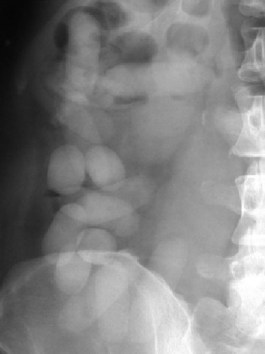

SIGNO DEL PSEUDOTUMOR

En la radiografía simple de abdomen, cuando un asa intestinal está obstruida por un vólvulo se llena de líquido y produce una falsa imagen de masa con densidad de partes blandas (flechas) que no debe confundirse con un tumor.

Este signo debe diferenciarse de las asas rellenas de líquido en la obstrucción mecánica simple. En la obstrucción en asa cerrada, la presencia del signo del pseudotumor indica que un asa intestinal se encuentra fija y permanece en la misma posición en todas las proyecciones.

En la imagen, pseudomasa causada por asas distendidas, con líquido, en la obstrucción intestinal.